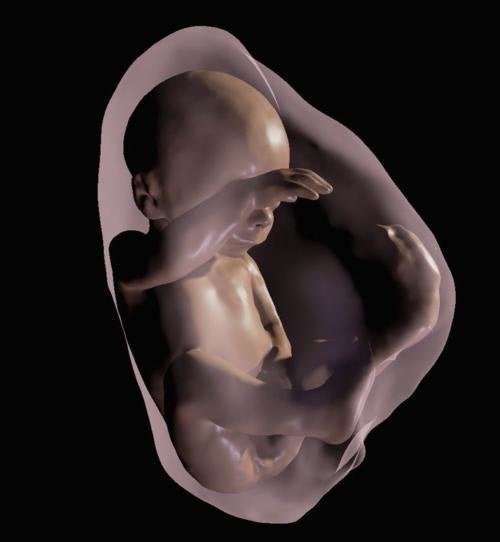

Groundbreaking technology is being used to create 3D models of unborn babies, that parents can interact with using virtual reality headsets.

The research, which is currently being trialed in a clinic in Rio de Janeiro, combines ultrasound imagery with an MRI scan, to build a three dimensional model from inside the womb.

The model details anatomical features of the foetus so precisely that researchers claim the model bares a remarkable similarity to the postnatal appearance of the newborn baby.

Dr. Heron Werner, said: “It provides fetal images that are sharper and clearer than ultrasound and MR images viewed on a traditional display.”

Incorporating information about the womb, placenta, umbilical cord, and even internal organs, the technology will be valuable for doctors who are tracking the development of the child.

Using a virtual reality headset, the model is ‘brought to life’ as parents and medics can listen to the baby’s heartbeat and look out for any potential health problems.

This immersive visualisation is the first of it’s kind, developed by the Radiological Society of North America, and obviously has numerous implications for both the industry, and parents who want to watch their child grow.

One of the most important medical benefits is the ability for doctors to assess foetal airways patency – the state of airways being open and unblocked - which is an important issue for developing babies.